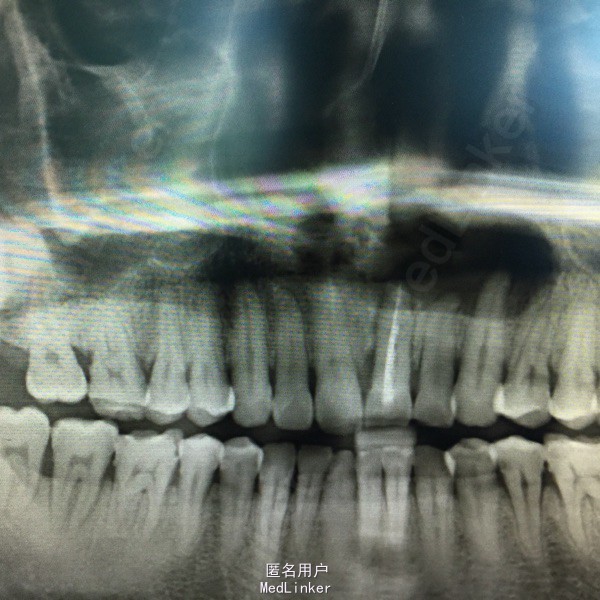

左上前牙腭侧区肿胀伴溢脓半年。

查:21牙体变色,叩(十),松约1mm,腭侧粘膜轻微肿胀,压之溢脓,有治疗史。全景牙片示:21、22、23根尖区有5x3cm大小阴影,边缘可见白色阻射线。